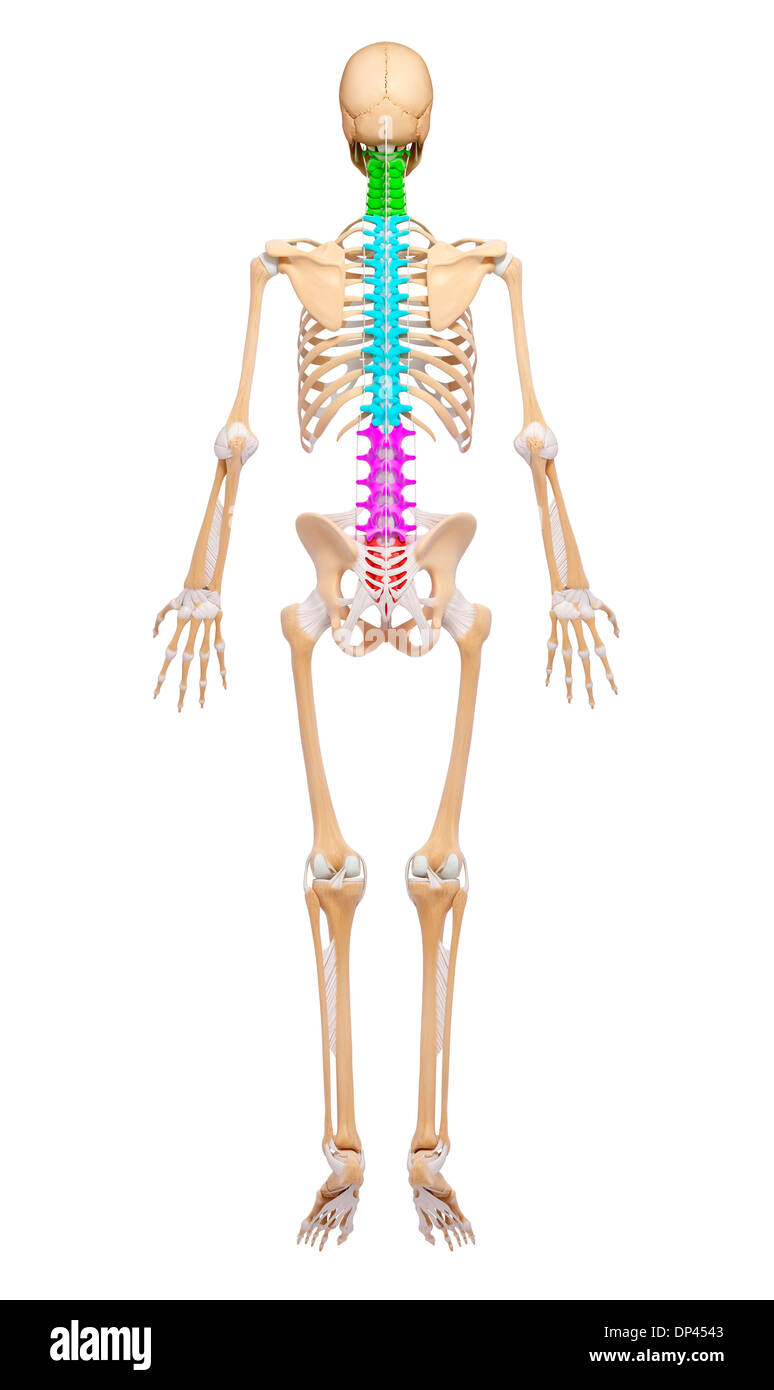

Human Skeleton, artwork Banque D'Imageshttps://www.alamyimages.fr/image-license-details/?v=1https://www.alamyimages.fr/human-skeleton-artwork-image65245379.html

Human Skeleton, artwork Banque D'Imageshttps://www.alamyimages.fr/image-license-details/?v=1https://www.alamyimages.fr/human-skeleton-artwork-image65245379.htmlRFDP4543–Human Skeleton, artwork